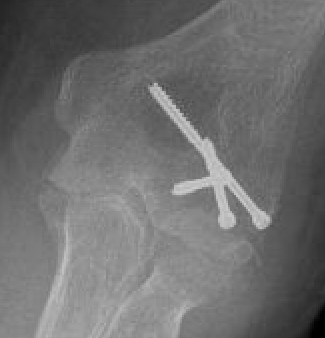

Capitellum fracture with radial head fracture

Capitellum fracture with radial head dislocation due to LCL injury

Concomitant injuries

Radial head

Watts et al JBJS Br 2007

- 79 capitellar fractures

- 24% had a radial head fracture as well

LCL

Dubberley et al JBJS Am 2006

- 27 capitellum fractures treated with surgery

- 41% had associated LCL injuries

- 7/11 LCL injuries were avulsion fractures of the lateral epicondyle